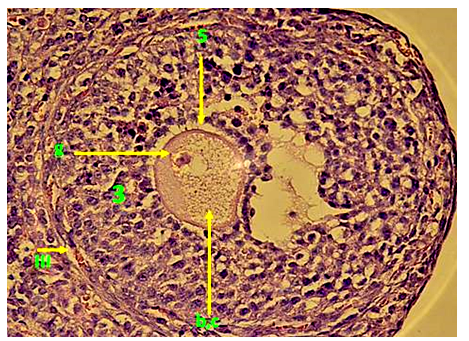

1. After three days of Adriamycin drug injection (A-I), it has been noted that the Graafian follicles were the most affected ovarian follicles. The toxicity of the drug caused the disappearance of the most of the natural Graafian follicles from the ovary. Furthermore, most of the follicles that have been seen in the ovary during this period are decomposed follicles with abnormal structures. In addition, a complete destruction of the Cumulus oophorous has been observed, with the spread of the Granulosa cells in the antrum. This is due to the loss of contact within the Granulosa cells, and the rush of its nuclei toward the antrum and the Zona pellucid. Consequently, this causes the destruction of the chromatin in some cells and its accumulation on the basement membrane of other cells, and thinning of the thickness of Theca folliculi. In addition, we noticed the presence of spaces in theca folliculi and migration of the Granulosa cells from the basement membrane, and partly the breadth of the Zonapellucidabecause of the loss of desmosomes between the oocyte and the cells. Regarding the Oocyte, the position of the nucleus is laterally with partial Granulosa decomposition of the nucleus membrane. In addition to the decomposition of the nucleus in some Graafian follicles (fig. 3), a clear reduction in the divisive ability of the Granulosa cells is seen compared to the normal control (fig. 4).

Fig. 3: Transverse section in Degradable Graafian follicles in the ovary of females injected with Adriamycin drug without protective dose (the first time (AI)-(H & Ix400) Fig. 4: Transverse section in Degradable Graafian follicles in the ovary of females injected with Adriamycin drug without protective dose (the first time (AI)-(Ki67x400)